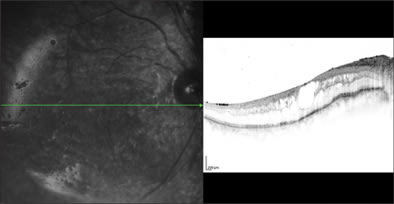

On postoperative day 2, the retinal lesions showed demarcation, suggesting regression of the active process (Figures 4 and 5). Her vision in OD had now declined to 20/600. Keratic precipitates were noted to regress in size and number. The retinal lesions continued to decrease over the course of the 10 days with a concomitant improvement of her vision to 20/400, so that we were comfortable to discharge the patient on oral acyclovir 800 mg 5 times per day. Acyclovir therapy was maintained over a total of 3 months. At 6 months postoperatively, we opted to remove the silicone oil during cataract surgery on her right eye. Subsequently, ocular hypotony developed in OD with choroidal detachments (Figure 6), which required a silicone oil refill. An aspirate from the vitreous cavity obtained during the latter procedure was again positive for V. zoster immunoglobulin A by immunofluorescence assay, which prompted us to resume oral acyclovir therapy with 400 mg 3 times per day, along with 8 mg prednisone po and prednisone ointment twice per day for her right eye.

Figure 5. Spectralis OCT imaging on postop day 2. A polycystoid macular edema, with preserved retinal architecture was seen (above), while a (representative) scan at the superotemporal vascular arcade revealed an thinned, atrophic retina (below). Left fundus images are taken in infrared modus, whereby the green arrow corresponds with the direction OCT scans on the right.